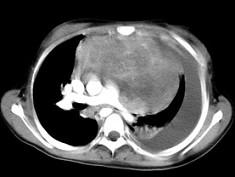

患者胸痛胸闷,CT如图所示,最可能的诊断为 ( )A、表皮样囊肿B、淋巴瘤C、恶性畸胎瘤D、侵袭性胸腺瘤E、良性胸腺瘤

问题 患者胸痛胸闷,CT如图所示,最可能的诊断为 ( )

选项 A、表皮样囊肿 B、淋巴瘤 C、恶性畸胎瘤 D、侵袭性胸腺瘤 E、良性胸腺瘤

答案 D